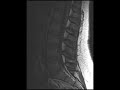

Dilated Epidural Venous Plexus

These images show multiple prominent serpiginous T1 and T2 hypointense structures in the ventral epidural space posterior to the L4 and L5 vertebral bodies resulting in mass effect on the thecal sac with crowding of the cauda equina.This is most compatible with dilation of the epidural venous plexus in this pregnant patient. Mass effect from the gravid uterus results in redirection of venous flow through collateral of the vertebral plexus. This is usually a reversible phenomenon and shouldn’t be confused for epidural hematoma or a vascular malformation.